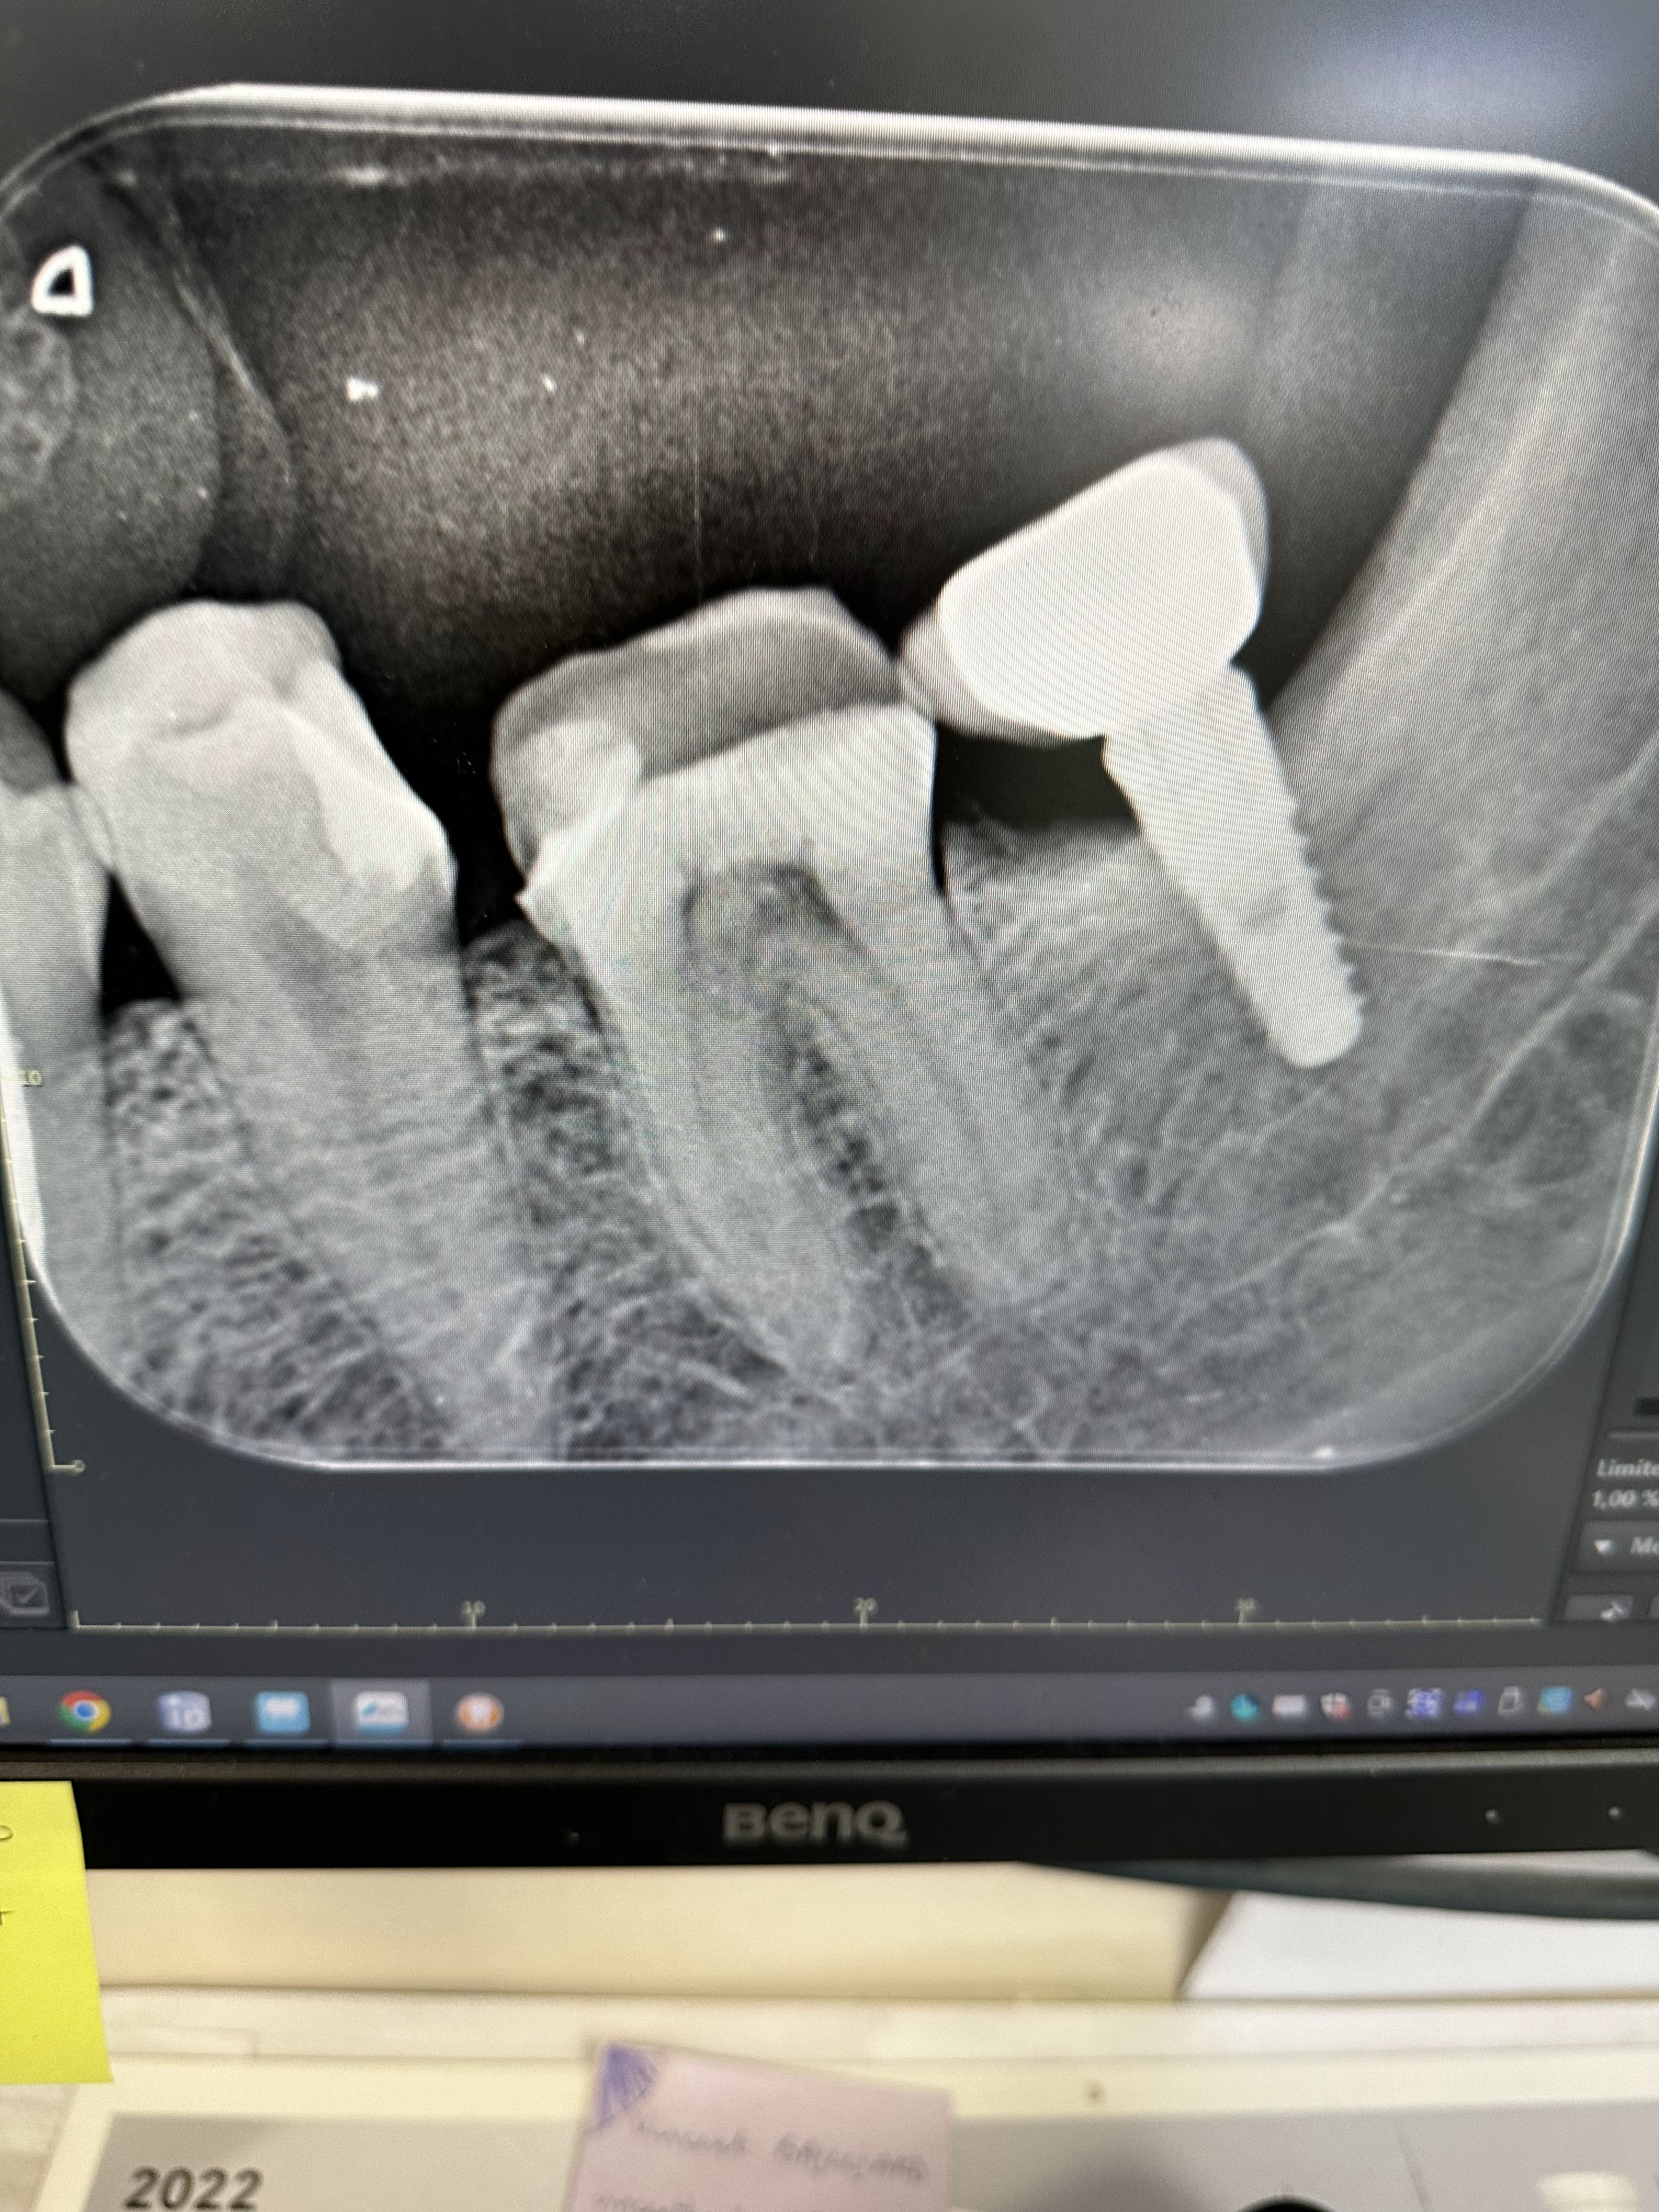

Je ne connais pas le docteur vanhelst car je suis suivie par le docteur Longueval Je regrette écrire cet avis mais il est important de partager cette expérience pour d’autres. Le docteur Longueval a posé un implant qui a dû être retiré car mal posé ! Il n’y avait ni besoin d’un implant ni la place pour le poser ! J’ai eu des douleurs rapidement, cependant il a refusé de me recevoir en RDV. Heureusement j’ai pu le faire enlever par un dentiste très professionnel ! L’implant a été retiré en deux heures car très mal posé ! Les douleurs, l’argent dépensé pour rien mais surtout un sérieux manque de considération des patients. J’étais patiente depuis 10 ans …regardez juste la photo de l’implant ! Cela parle de lui même !